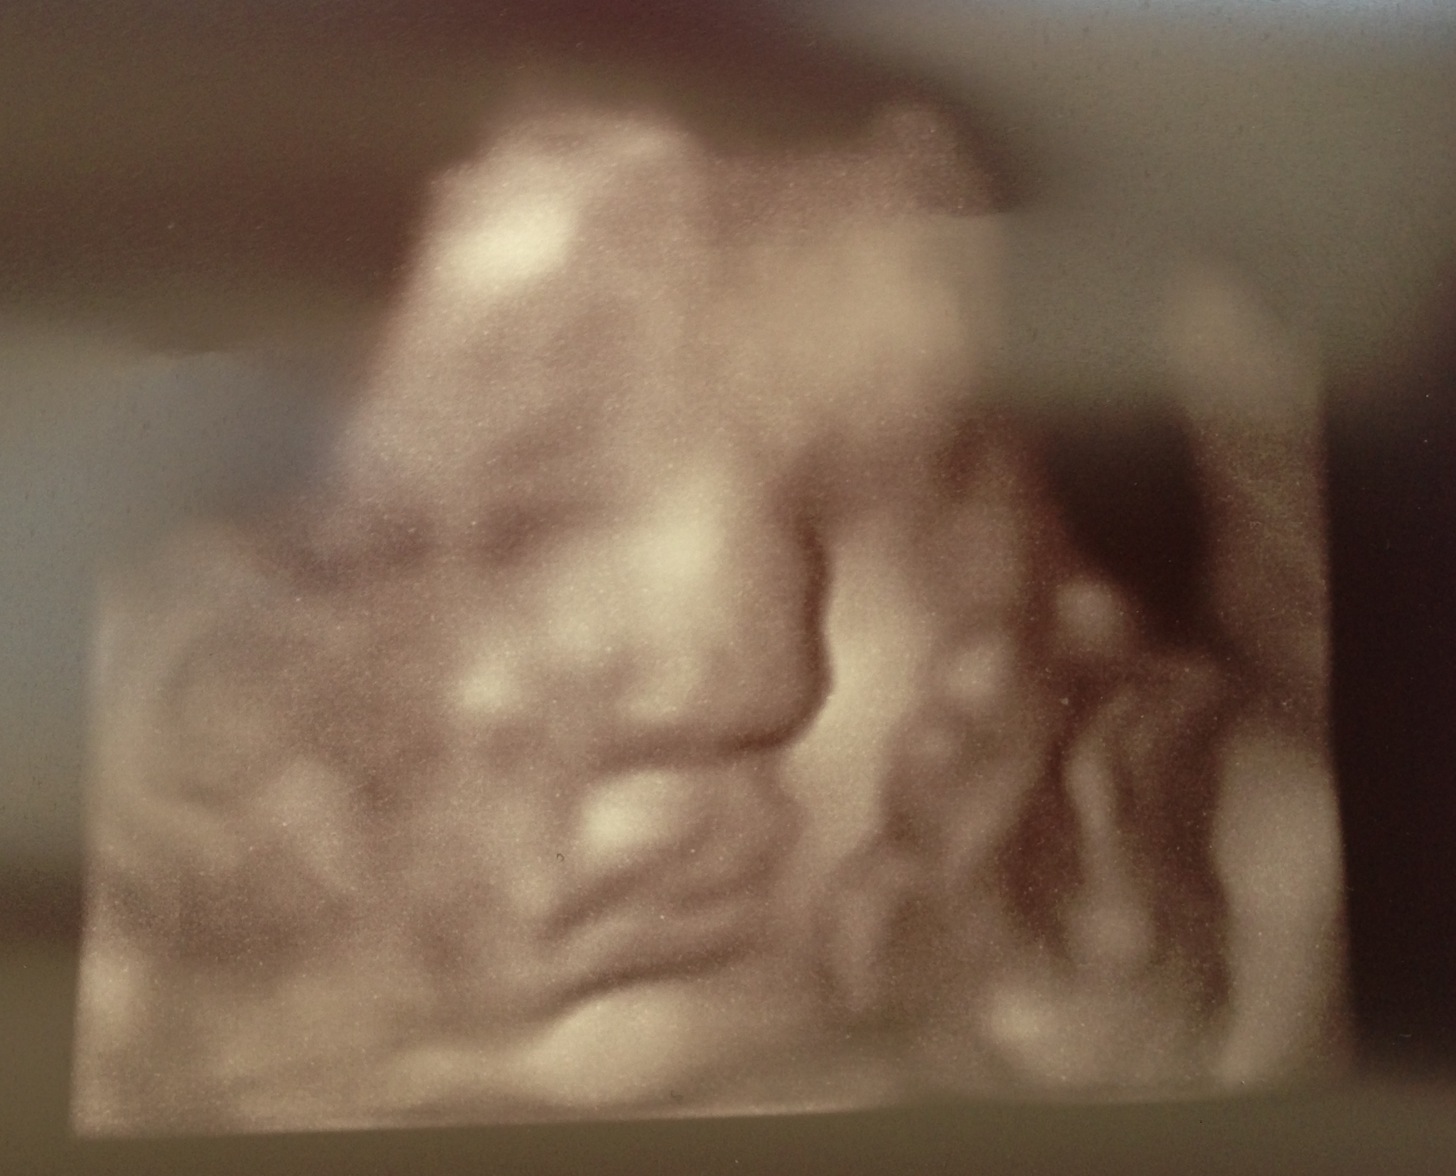

The baby actually made her first appearance front and center in the 8th month.

Yup, for every other visit when there was a chance to get a picture during the sonogram, she managed to turn away from the camera. But this week she came out of hiding and you can easily make out many of her features. (Don’t mind the placenta smooshing into her face)

She is rapidly growing, and if she continues on this pace… we may also be calling her “The Big Hurt”. But no matter what, she is a Hall of Famer in my eyes already.